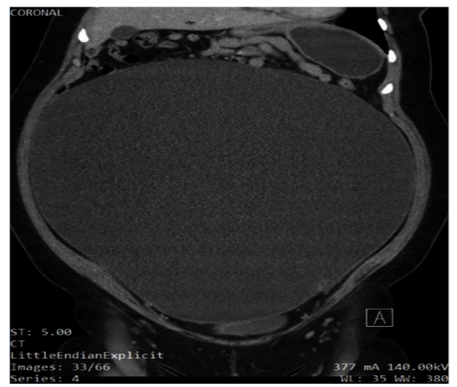

On examination, the patient appeared to be obese, welldeveloped, anxious, and cooperative. She was not able to tolerate a speculum examination due to the pain. There was no pulsatile abdominal mass, guarding of the abdomen, nor any generalized and/or rebound tenderness or rigidity. The lower left quadrant of the patient’s abdomen was tender with mild distention and normal bowel sounds were heard. An elevated blood pressure on admission (145/89) was noted. The urinalysis was unremarkable. Blood analysis showed hypochromic, microcytic anemia (10.3 g/ dL) with +1 anisocytosis (generally associated with iron deficiency anemia [11], and mild elevated chloride (109 mEq/L) and elevated glucose (109 mg/dL) levels. A pelvic ultrasound reported a normal uterus with no endometrial abnormalities, and the right ovary appeared normal. The left ovary was not visualized (Figures 1 and Figure 2). A large cystic structure was seen, whose origin was unknown. An abdominal/pelvic computerized tomography (CT) with contrast found a 36 cm cyst lesion filling the abdominal and pelvic cavity which appeared to originate from the left adnexa with a complicated hyperdense fluid or debris focus noted in the inferior margin of the cyst (Figure 3). The surrounding structures appeared unremarkable. There was a trace amount of fluid in the Pouch of Douglas. (Figure 4).

Figure 3: Sagittal slice of the patient’s abdomen on non-contrast CT showing the cyst occupying most of the abdominal cavity.